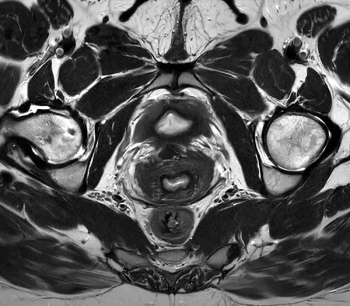

In an 18-study meta-analysis involving over 4,600 patients, researchers found that bpMRI and mpMRI had equivalent pooled negative predictive value (NPV) of 92 percent for clinically significant prostate cancer (csPCa).

A deep learning-enhanced ultra-fast bpMRI protocol offered similar sensitivity for csPCa as mpMRI with an 80 percent reduction in scan time, according to research findings presented at the European Congress of Radiology (ECR) conference.

In a multicenter study involving over 1,000 patients, a deep learning software offered comparable sensitivity and specificity for Gleason grade group > 2 tumors in comparison to radiologist interpretation.

In a recent literature review, researchers offered insights on current considerations with prostate MRI and discussed keys to effective use of the modality in screening for prostate cancer.